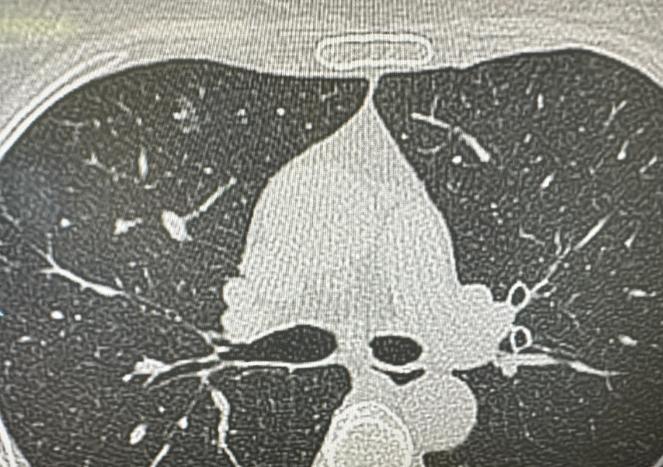

今天做这台肺结节手术,说实话我心里也一直悬着!患者四十多岁,去年就查出来右上肺有

肺结节切了又长,什么时候才能结束?这是一位55岁患者的真实经历。三年前,她因为右

肺原位癌和肺微浸润癌,差别真的很大吗?不少朋友体检发现磨玻璃结节,还带有一些磨玻

做了一台让我印象很深的肺癌手术,值得和大家分享一下!患者是一位50岁的女士,肺里